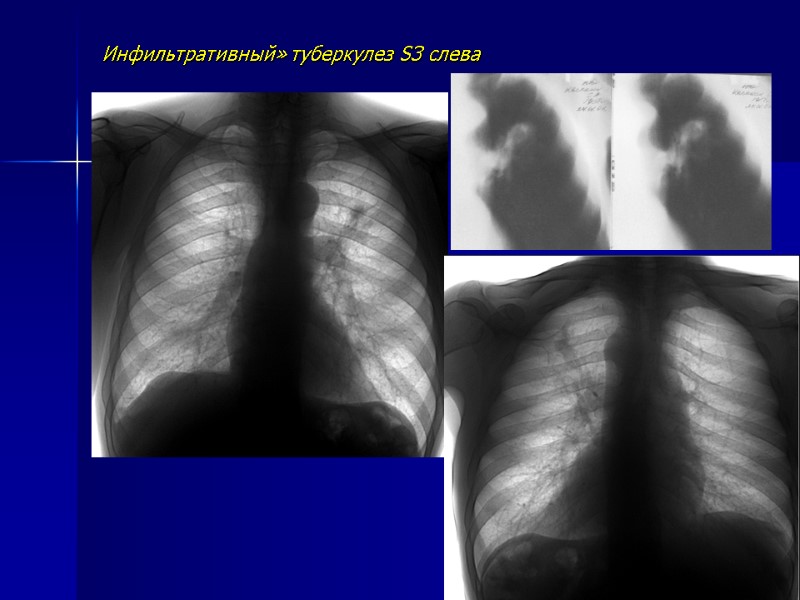

Инфильтративный» туберкулез S3 слева